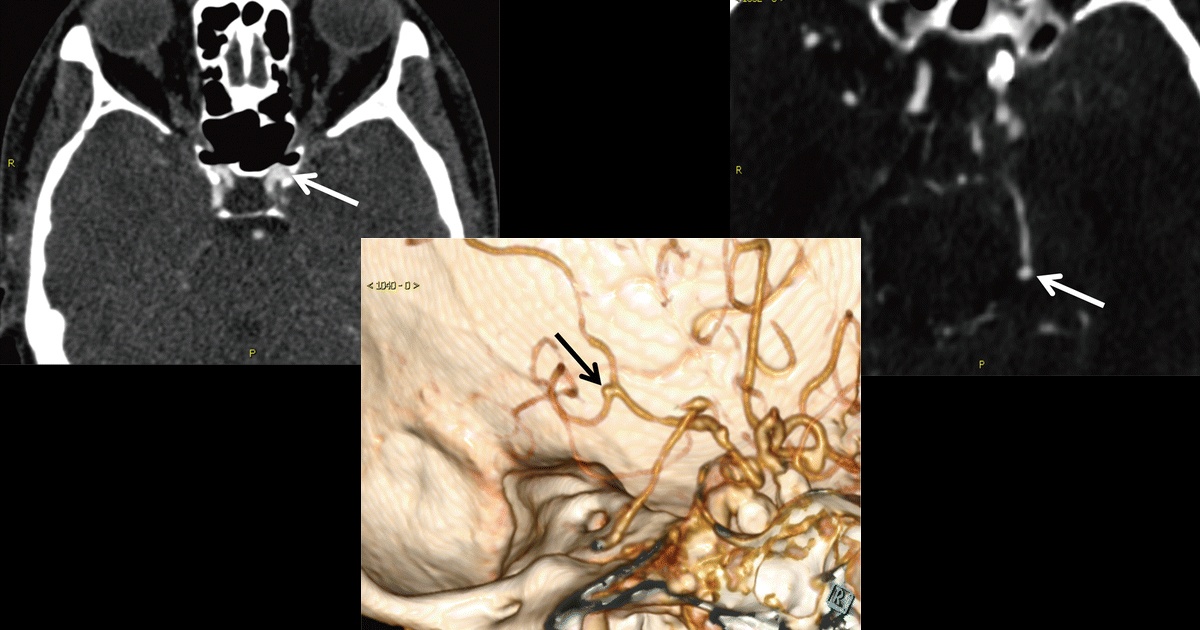

La detección de aneurismas cerebrales podría mejorar gracias al aprendizaje profundo, que busca realizar interpretaciones más precisas. La investigación titulada “Aprendizaje profundo para detectar aneurismas cerebrales con angiografía por TC”, tuvo como propósito desarrollar un algoritmo basado en este tipo de Inteligencia Artificial de alta sensibilidad para mejorar la detección de aneurismas cerebrales en imágenes de angiografía por Tomografía Computarizada (TC).

Para el desarrollo del aprendizaje profundo, de las 1068 angiografías por TC, 534 (688 aneurismas), fueron considerados para el entrenamiento del algoritmo y las 543 (649 aneurismas) restantes fueron utilizados para la validación del mismo. El algoritmo desarrollado fue capaz de detectas aneurismas cerebrales en imágenes con una sensibilidad de 97,5% es decir 633 de 649. Y detectó ocho nuevos aneurismas que no habían sido encontrados en los informes previos.